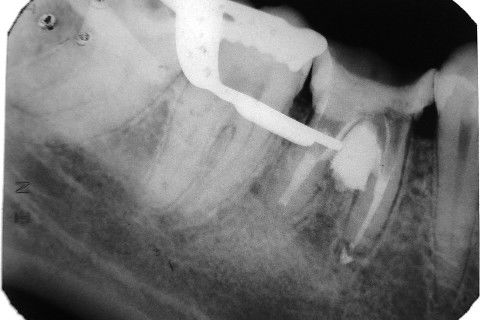

Retratamento de Canal, Tratamento de Perfuração, Restauração Provisória com Resina, Núcleo e Provisório.

RETRATAMENTO DE CANAL, TRATAMENTO DE PERFURAÇÃO, RESTAURAÇÃO PROVISÓRIA COM RESINA, NUCLEO E PROVISÓRIO.